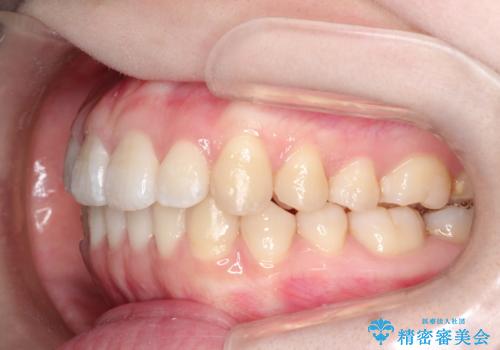

前歯にがたつきがあり、上下の歯が咬み合っていない状態でした。

歯列の横幅をひろげるのと、歯と歯の間をわずかに削ることにより、前歯のがたつきと、開咬を改善しました。